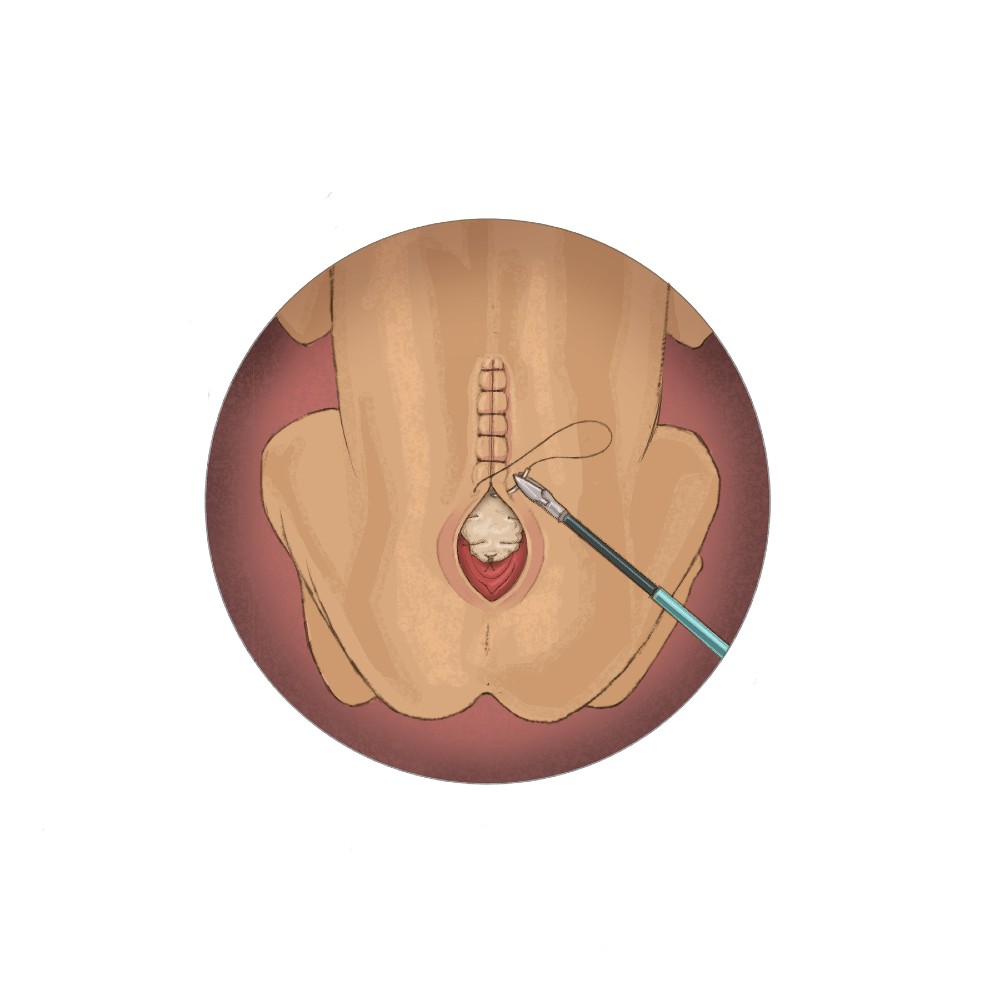

“Our primary outcome measure for the study is successful surgical closure of the spina bifida defect with a watertight patch that approximates native tissue and allows for the natural growth of the spinal cord,” Dr. Papanna says. “The procedure differs from in-utero repair, which requires a large incision on the uterus and delivery by cesarean section. Instead, we will repair the spina bifida defect in two layers through three small incisions in the uterus using fetoscopes and tiny surgical tools. The first layer will be closed using a NEOX®Cord 1K patch as a meningeal patch placed over the spinal cord, followed by a second layer of primary closure of the skin. Mothers will undergo vaginal delivery, unless there is an obstetrical indication for delivery by C-section.”

A digital image of the fetal repair site will be captured immediately after the repair, and efficacy of the fetoscopic repair will be assessed after birth by three blinded reviewers. Reviewing neurosurgeons are Arthur Day, MD, McGovern Medical School and UTHealth Neurosciences in Houston; Bradley Edward Weprin, MD, UT Southwestern Medical Center in Dallas; and John Honeycutt, MD, Cook Children’s Hospital in Dallas.